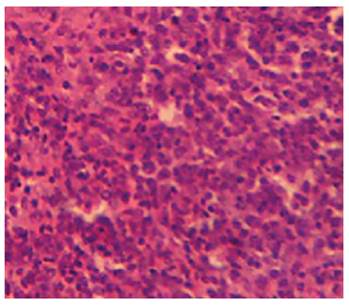

Effect of MSEAO on vital organs. Gross and histopathological examinations showed no significant (P > 0.05) lesions in the vital tissues (Bursa of Fabricius and spleen) examined as compared to the control group. See Figures 1 and 2.

Figure 2 Spleen of chicken in group 1 showing no obvious lesions 48 h post-administration. H&E x 200.